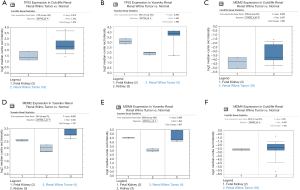

Next, we analyzed the TP53 expression levels specifically in WT. A significant difference existed between the levels of TP53 expression in WT samples and normal samples in the Cutcliffe Renal dataset [P value =0.010, fold change (FC) =1.976]; however, TP53 expression was not significantly different between tumor samples and normal samples in the Yusenko Renal dataset (P value =0.094, FC =1.984) (Figure 2A,B).

Subsequently, we also explored the expression levels of the genes involved in the TP53 signaling pathway. The results showed that MDM2 was significantly overexpressed in the Yusenko Renal dataset (P value =0.05, FC =1.747), but not in the Cutcliffe Renal dataset (P value =0.058, FC =1.955) (Figure 2C,D). The expression levels of MDM4 showed no significant difference in the Yusenko Renal dataset (P value =0.055, FC =1.837) or in the the Cutcliffe Renal dataset (P value =0.501, FC =−1.001) (Figure 2E,F). These results indicated that the TP53 signaling pathway genes are differentially expressed in WT and, therefore, may serve an important role in the tumorigenesis and prognosis of WT.